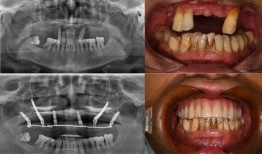

佛山种牙爆料事件视频曝光,揭露行业乱象引发关注

最近佛山那边的种牙事件可是闹得沸沸扬扬的,咱们得好好来聊聊这个话题。你有没有看过那个爆料视频?简直让人瞠目结舌啊!事件回顾:佛山...